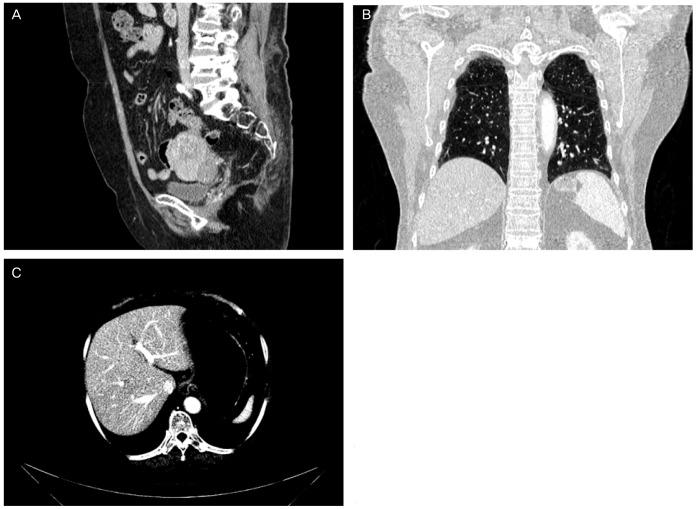

Primary vaginal cancer represents only 1% to 2% of malignant neoplasm of the female genital tract. Here, we report a 68-year-old woman who showed a vaginal tumor extending to urethra and clitoris, a 10 cm-sized mass in left adnexa and multiple metastases in lung and liver. Vaginal biopsy showed squamous cell carcinoma of vagina and she was diagnosed as International Federation of Gynecology and Obstetrics stage IVB vaginal cancer. Palliative surgery including left salpingectomy, tumorectomy, and clitoris mass excision was performed. Concurrent chemoradiation therapy (CCRT) with six cycles of 5-fluorouracil and cisplatin was administered. The patient had a complete remission of 20 months after treatment. At a 40-month follow-up, there was no evidence of local recurrence or distant metastasis. We can suggest that CCRT is very effective in treating primary squamous cell carcinoma of the vagina, not only in locally advanced but also systemically involved vaginal cancer in selected cases.

原发性阴道癌仅占女性生殖道恶性肿瘤的1%至2%。在此,我们报告一名68岁女性,其阴道肿瘤延伸至尿道和阴蒂,左侧附件有一个10厘米大小的肿块,肺部和肝脏有多处转移。阴道活检显示为阴道鳞状细胞癌,她被诊断为国际妇产科联盟IVB期阴道癌。进行了姑息性手术,包括左侧输卵管切除术、肿瘤切除术和阴蒂肿块切除术。给予了六个周期的5-氟尿嘧啶和顺铂同步放化疗(CCRT)。患者治疗后完全缓解20个月。在40个月的随访中,没有局部复发或远处转移的证据。我们可以认为,CCRT在治疗原发性阴道鳞状细胞癌方面非常有效,不仅对局部晚期阴道癌有效,而且对某些系统受累的阴道癌也有效。